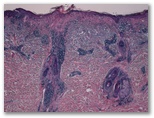

a) La dermatomiositis

b) el lupus eritematoso (dermatitis lupus)

c) Drogas - tipo de interfaz

d) El liquen plano, el tipo de parte atrófica

e) enfermedad de injerto contra huésped